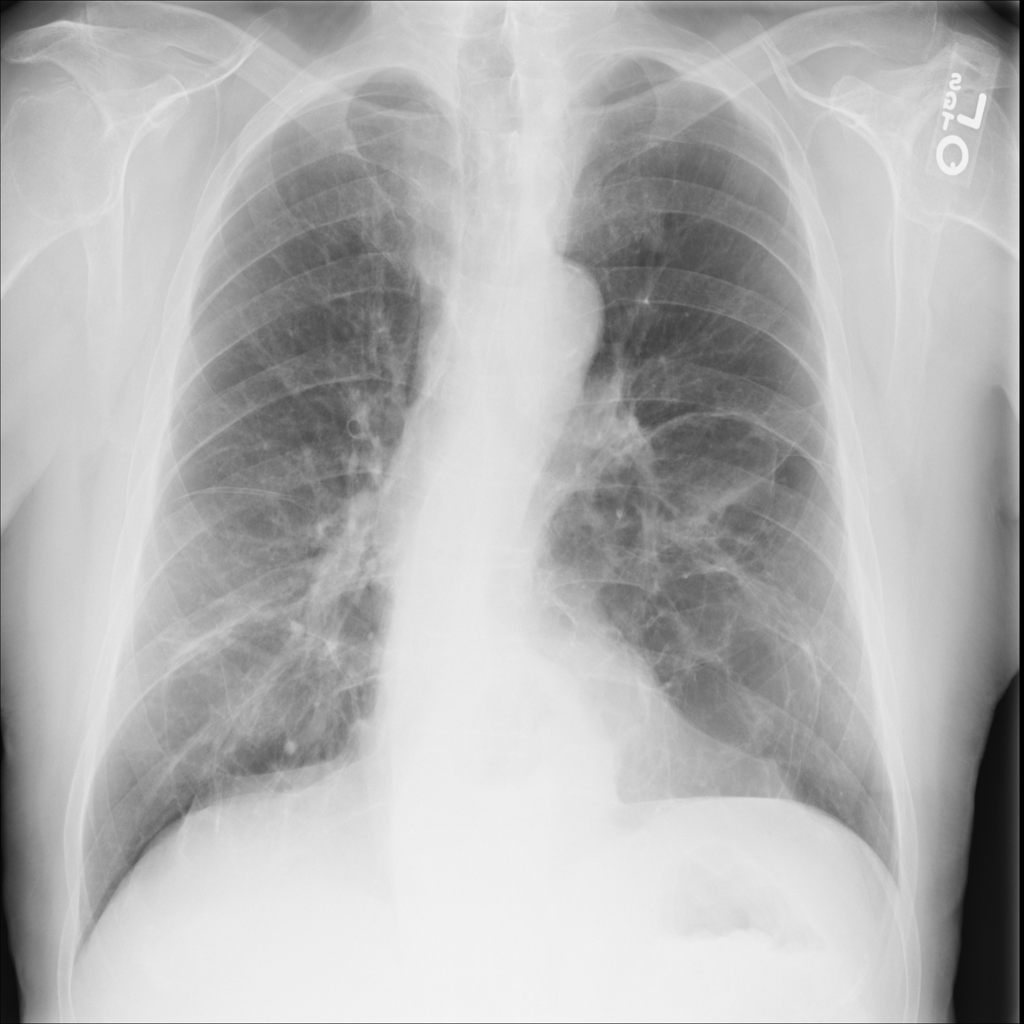

Showing up to 90 reference images for Hernia.

PAT-0ABD · IMG-000Hernia

PAT-0ABD · IMG-000

PA